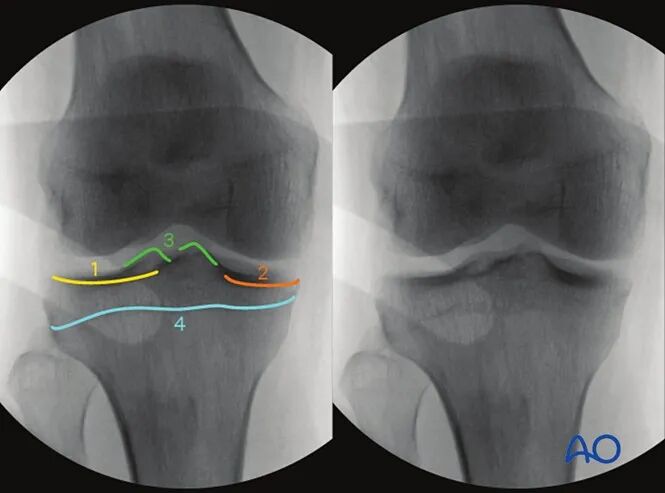

AO干货分享:

看胫骨平台是否平整的透视体位